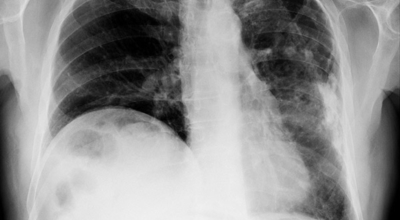

흉부 엑스레이

엑스레이 검사 방법으로는 실제 크기로 촬영하는 흉부 직접 촬영과 마이너스 70mm, 100mm 사진으로 촬영하는 간접 촬영이 있다고 하며, 일부 사람을 단체로 검사할 때 간접 촬영이 많이 활용돼요. 조사결과에 근거하면 결핵은 과감염성 결핵과 재활성성 결핵으로 구분되며, 기존 결핵은 소아결핵과 성인결핵으로 소속되는 경우가 많았어요. 인간면역결핍바이러스(HIV)에 감염된 사람들은 주로 과감염된 결핵을 보이 다고 알려져 있답니다.